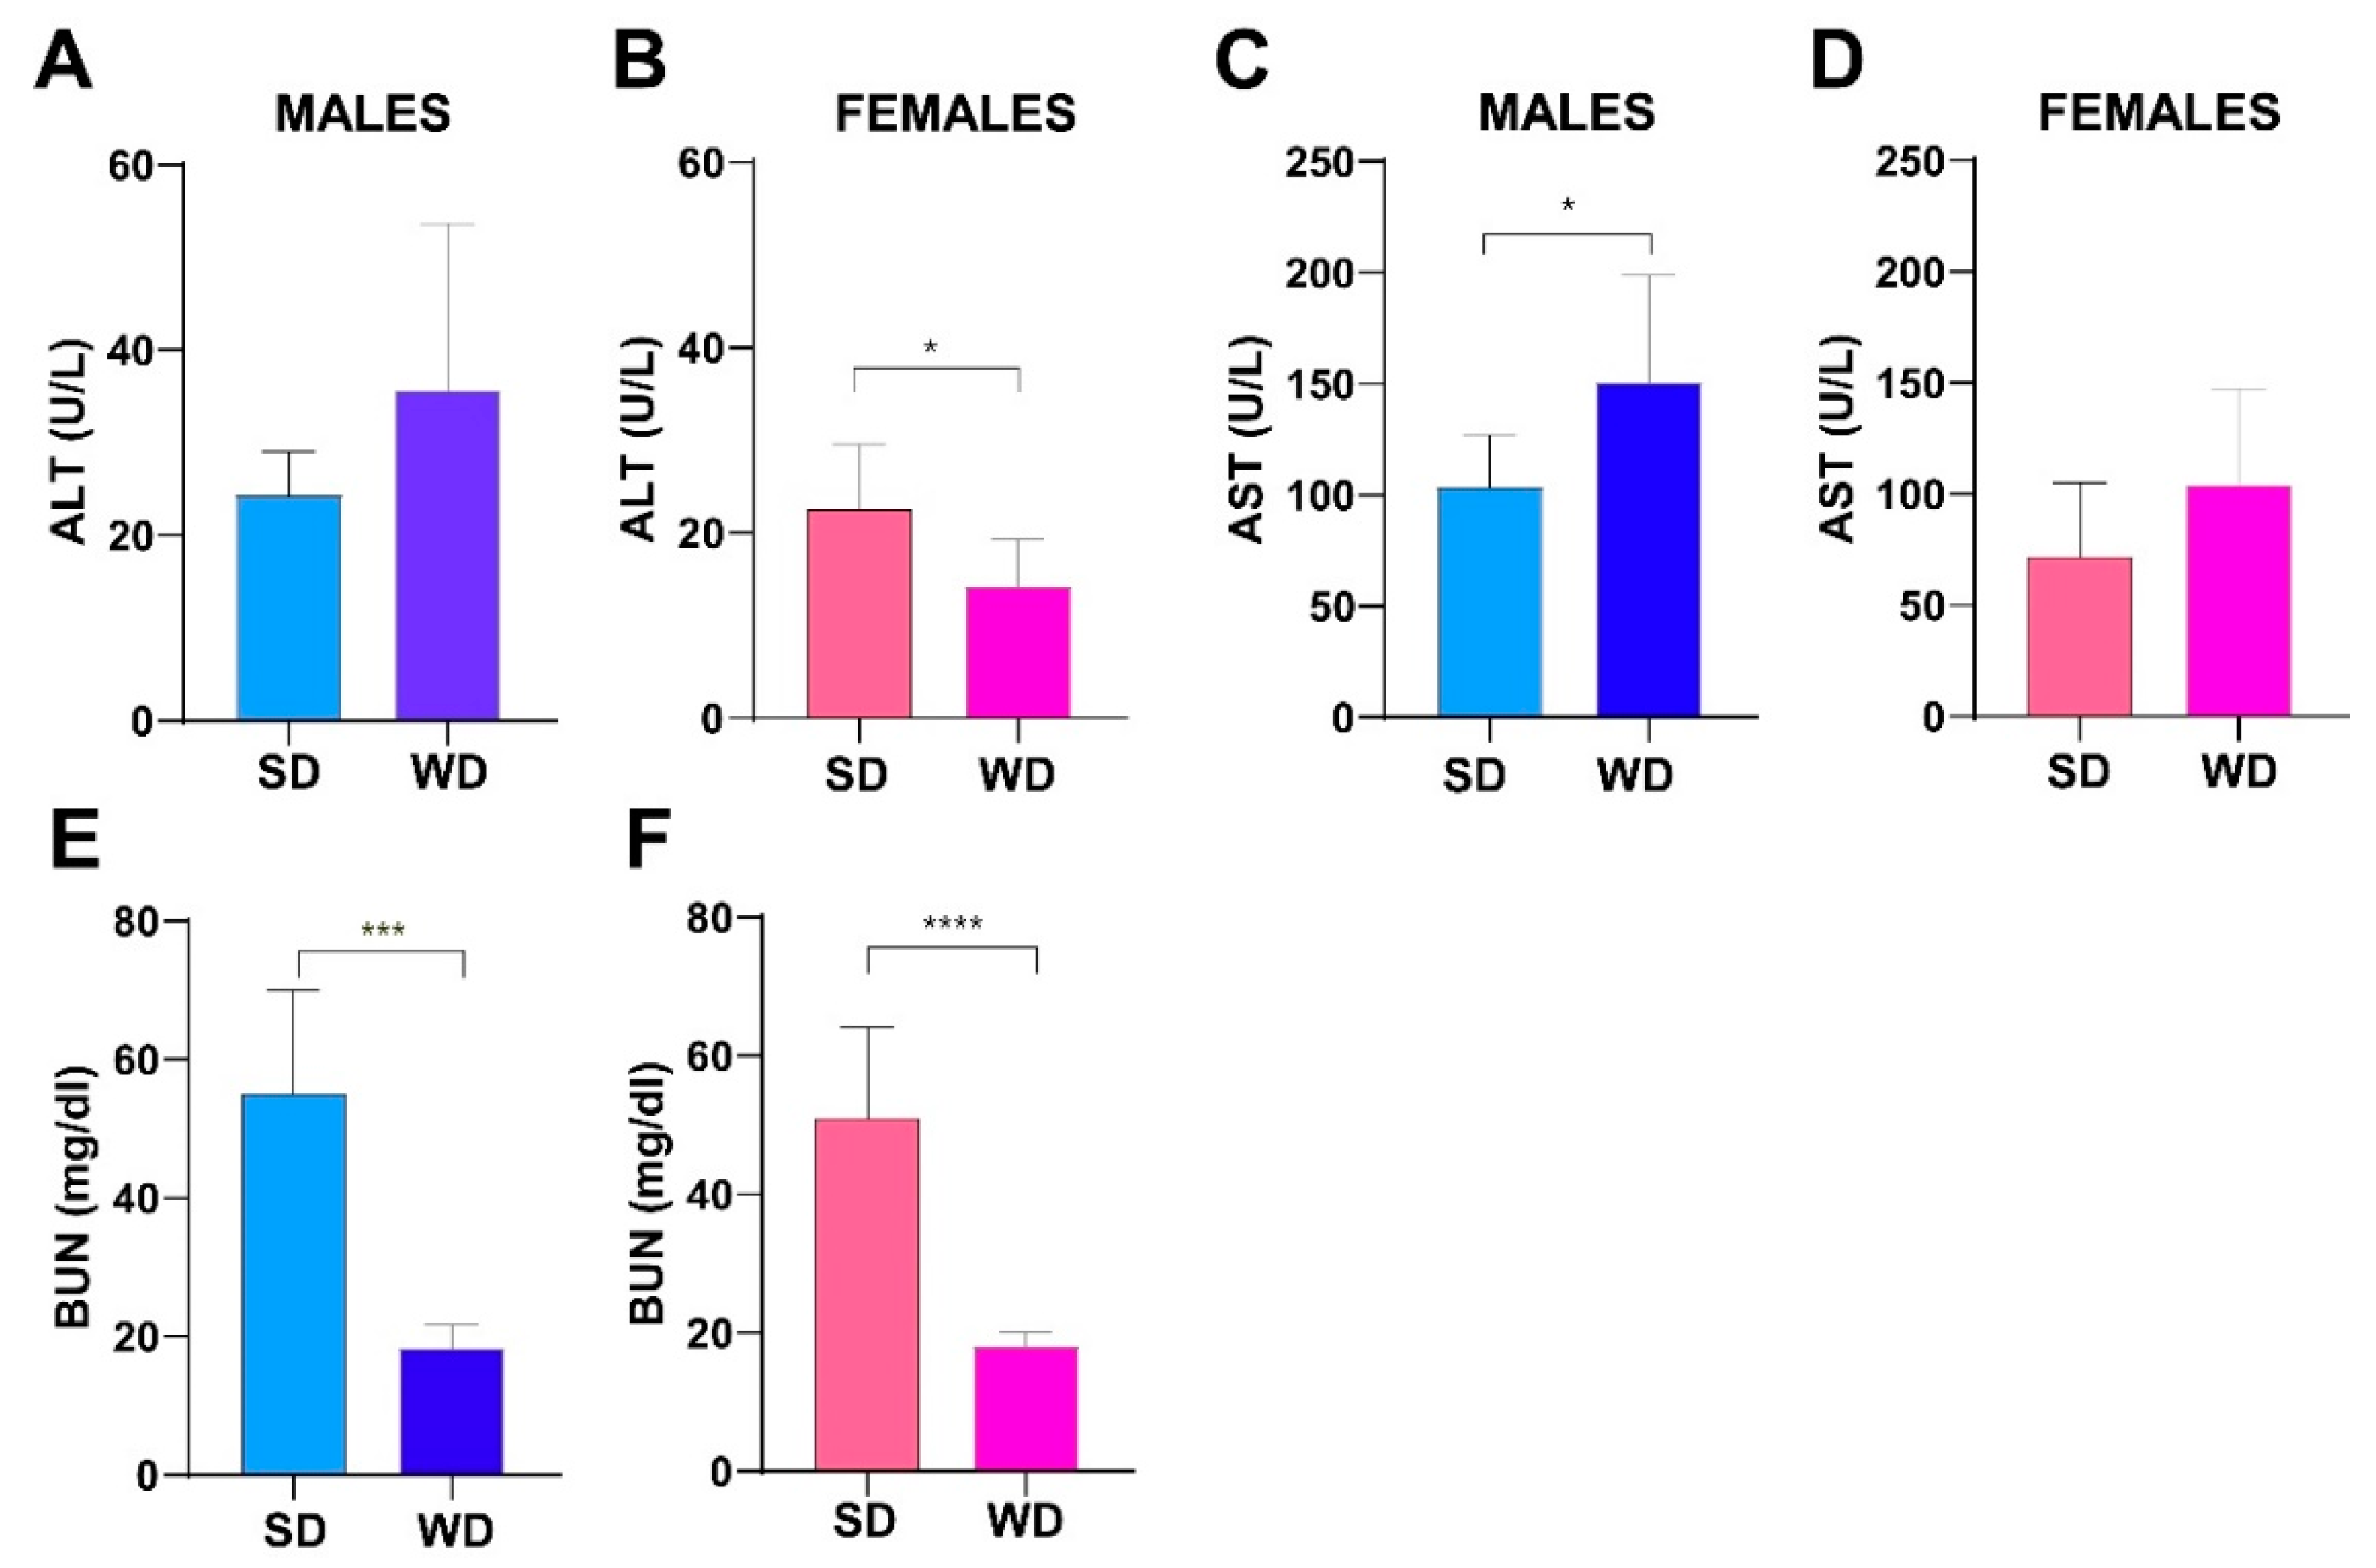

3.5. WD Induces Changes in Hepatic and Renal Biochemistry of C57Bl/6J Mice